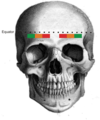

What are the steps for ASIA Classification?

- Determine if patient is in spinal shock

* check bulbocavernosus reflex - Determine neurologic level of injury

lowest segment with intact sensation and antigravity (3 or more) muscle function strength

in regions where there is no myotome to test, the motor level is presumed to be the same as the sensory level.

- Determine whether the injury is COMPLETE or INCOMPLETE

COMPLETE defined as (ASIA A)

no voluntary anal contraction (sacral sparing) AND

0/5 distal motor AND

0/2 distal sensory scores (no perianal sensation) AND

bulbocavernosus reflex present (patient not in spinal shock)

INCOMPLETE defined as

voluntary anal contraction (sacral sparing)

sacral sparing critical to determine complete vs. incomplete

OR palpable or visible muscle contraction below injury level OR

perianal sensation present

ASIA Grades